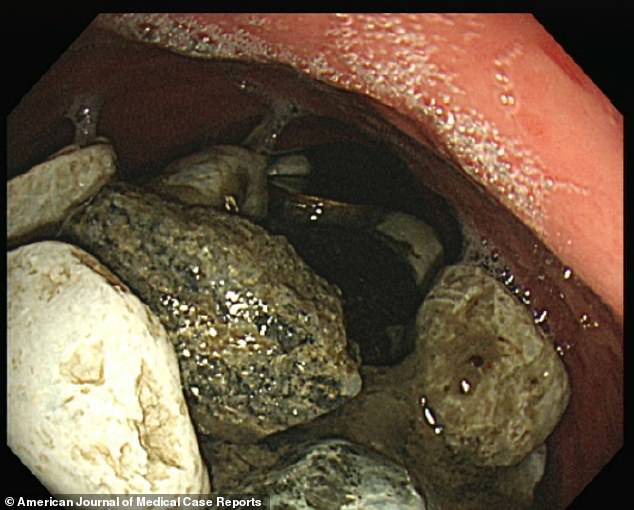

Ούτε ένα πετραδάκι ούτε δυο. Οι γιατροί μόλις είδαν την ακτινογραφία του στομάχου ενός 54χρονου άνδρα από τη Νότια Κορέα, έφριξαν.

Ολόκληρο το στομάχι του είχε γεμίσει μικρά πετραδάκια τα οποία έτρωγε ο άνδρας προκειμένου να καταπολεμήσει το άγχος και την ανησυχία του. Και όταν λέμε είχε γεμίσει κυριολεκτούμε.

Εκτός από πετραδάκια ο άνδρας έτρωγε και κέρματα και λίγα κουμπιά. Αλλά προτιμούσε ως επι το πλείστον τα πετραδάκια. Εκείνα, λέει, τον βοηθούσαν καλύτερα. Μέχρι που το στομάχι του δεν άντεξε και ο άνδρας άρχισε να πονάει φριχτά. Πήγε στο νοσοκομείο, οι γιατροί τον εξέτασαν και επειγόντως τον έβαλαν στο χειρουργείο για να του αφαιρέσουν τα πετραδάκια.

Συνολικά αφαίρεσαν πέτρες και άλλα μικροαντικείμενα βάρους που ξεπερνά τα 2 κιλά.

Η εγχείρηση έγινε στο πανεπιστημιακό νοσοκομείο Ilsan Paik, λίγο έξω από τη Σεούλ. Ο καθηγητής Choi που ήταν επικεφαλής της ομάδας που αφαίρεσε τα πετραδάκια είπε ότι ήταν τόσα πολλά που ο ασθενής δεν μπορούσε καν να τα αποβάλλει με εμετό.